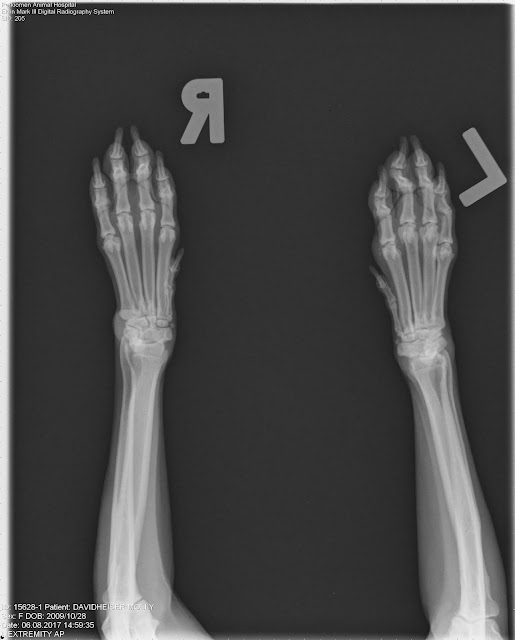

From www.floridaortho.com